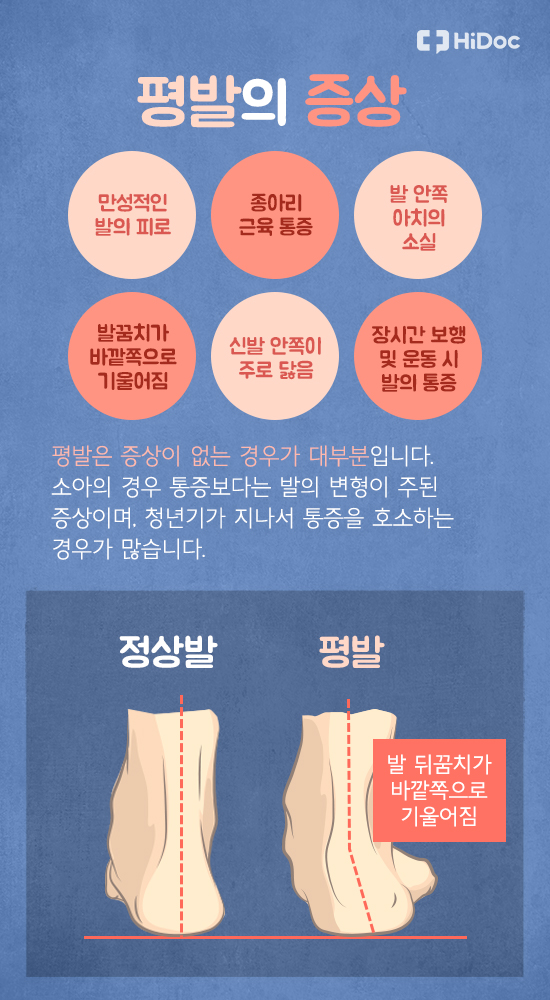

종아리는 우리 몸의 하체에서 가장 중요한 근육 중 하나인 **비복근(장딴지 근육)**과 가자미근으로 이루어져 있으며, 걷기, 달리기, 뛰기 등 다양한 움직임에 직접적으로 관여합니다. 따라서 종아리에 통증이 생긴다는 것은 다양한 원인과 관련이 있을 수 있으며, 이를 해결하기 위해서는 정확한 원인 파악과 적절한 대응이 필요합니다.

가장 흔한 원인 중 하나는 근육의 과도한 사용입니다. 장시간 걷거나 오르막길을 오르는 활동, 또는 운동 부족 상태에서 갑자기 과격한 운동을 한 경우 종아리 근육이 피로해져 통증이 발생합니다. 이 경우 일시적인 근육통으로 1~3일 안에 호전되지만 반복되면 만성 통증으로 발전할 수 있습니다.

장시간 앉아 있을 때 다리를 꼬지 않기, 허리를 펴고 앉기, 발을 평평하게 바닥에 붙이기 등의 자세 교정은 좌골신경통이나 허리 유래 통증을 줄이는 데 효과적입니다.